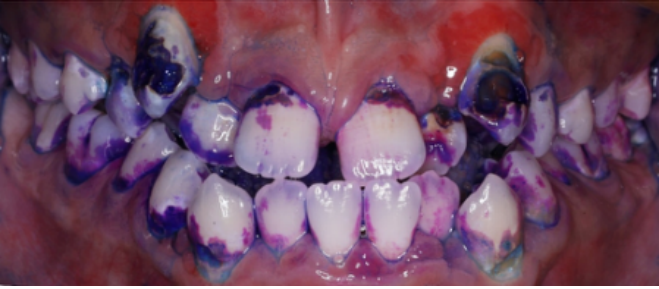

张晓萌医生为小宇做了详细检查,发现他的牙齿存在不同程度的龋坏,属于龋齿高风险人群。通过菌斑染色可见,牙齿表面附着大量菌斑,这些正是导致龋病的“罪魁祸首”。

治疗前口内照(菌斑染色,张晓萌医生提供)